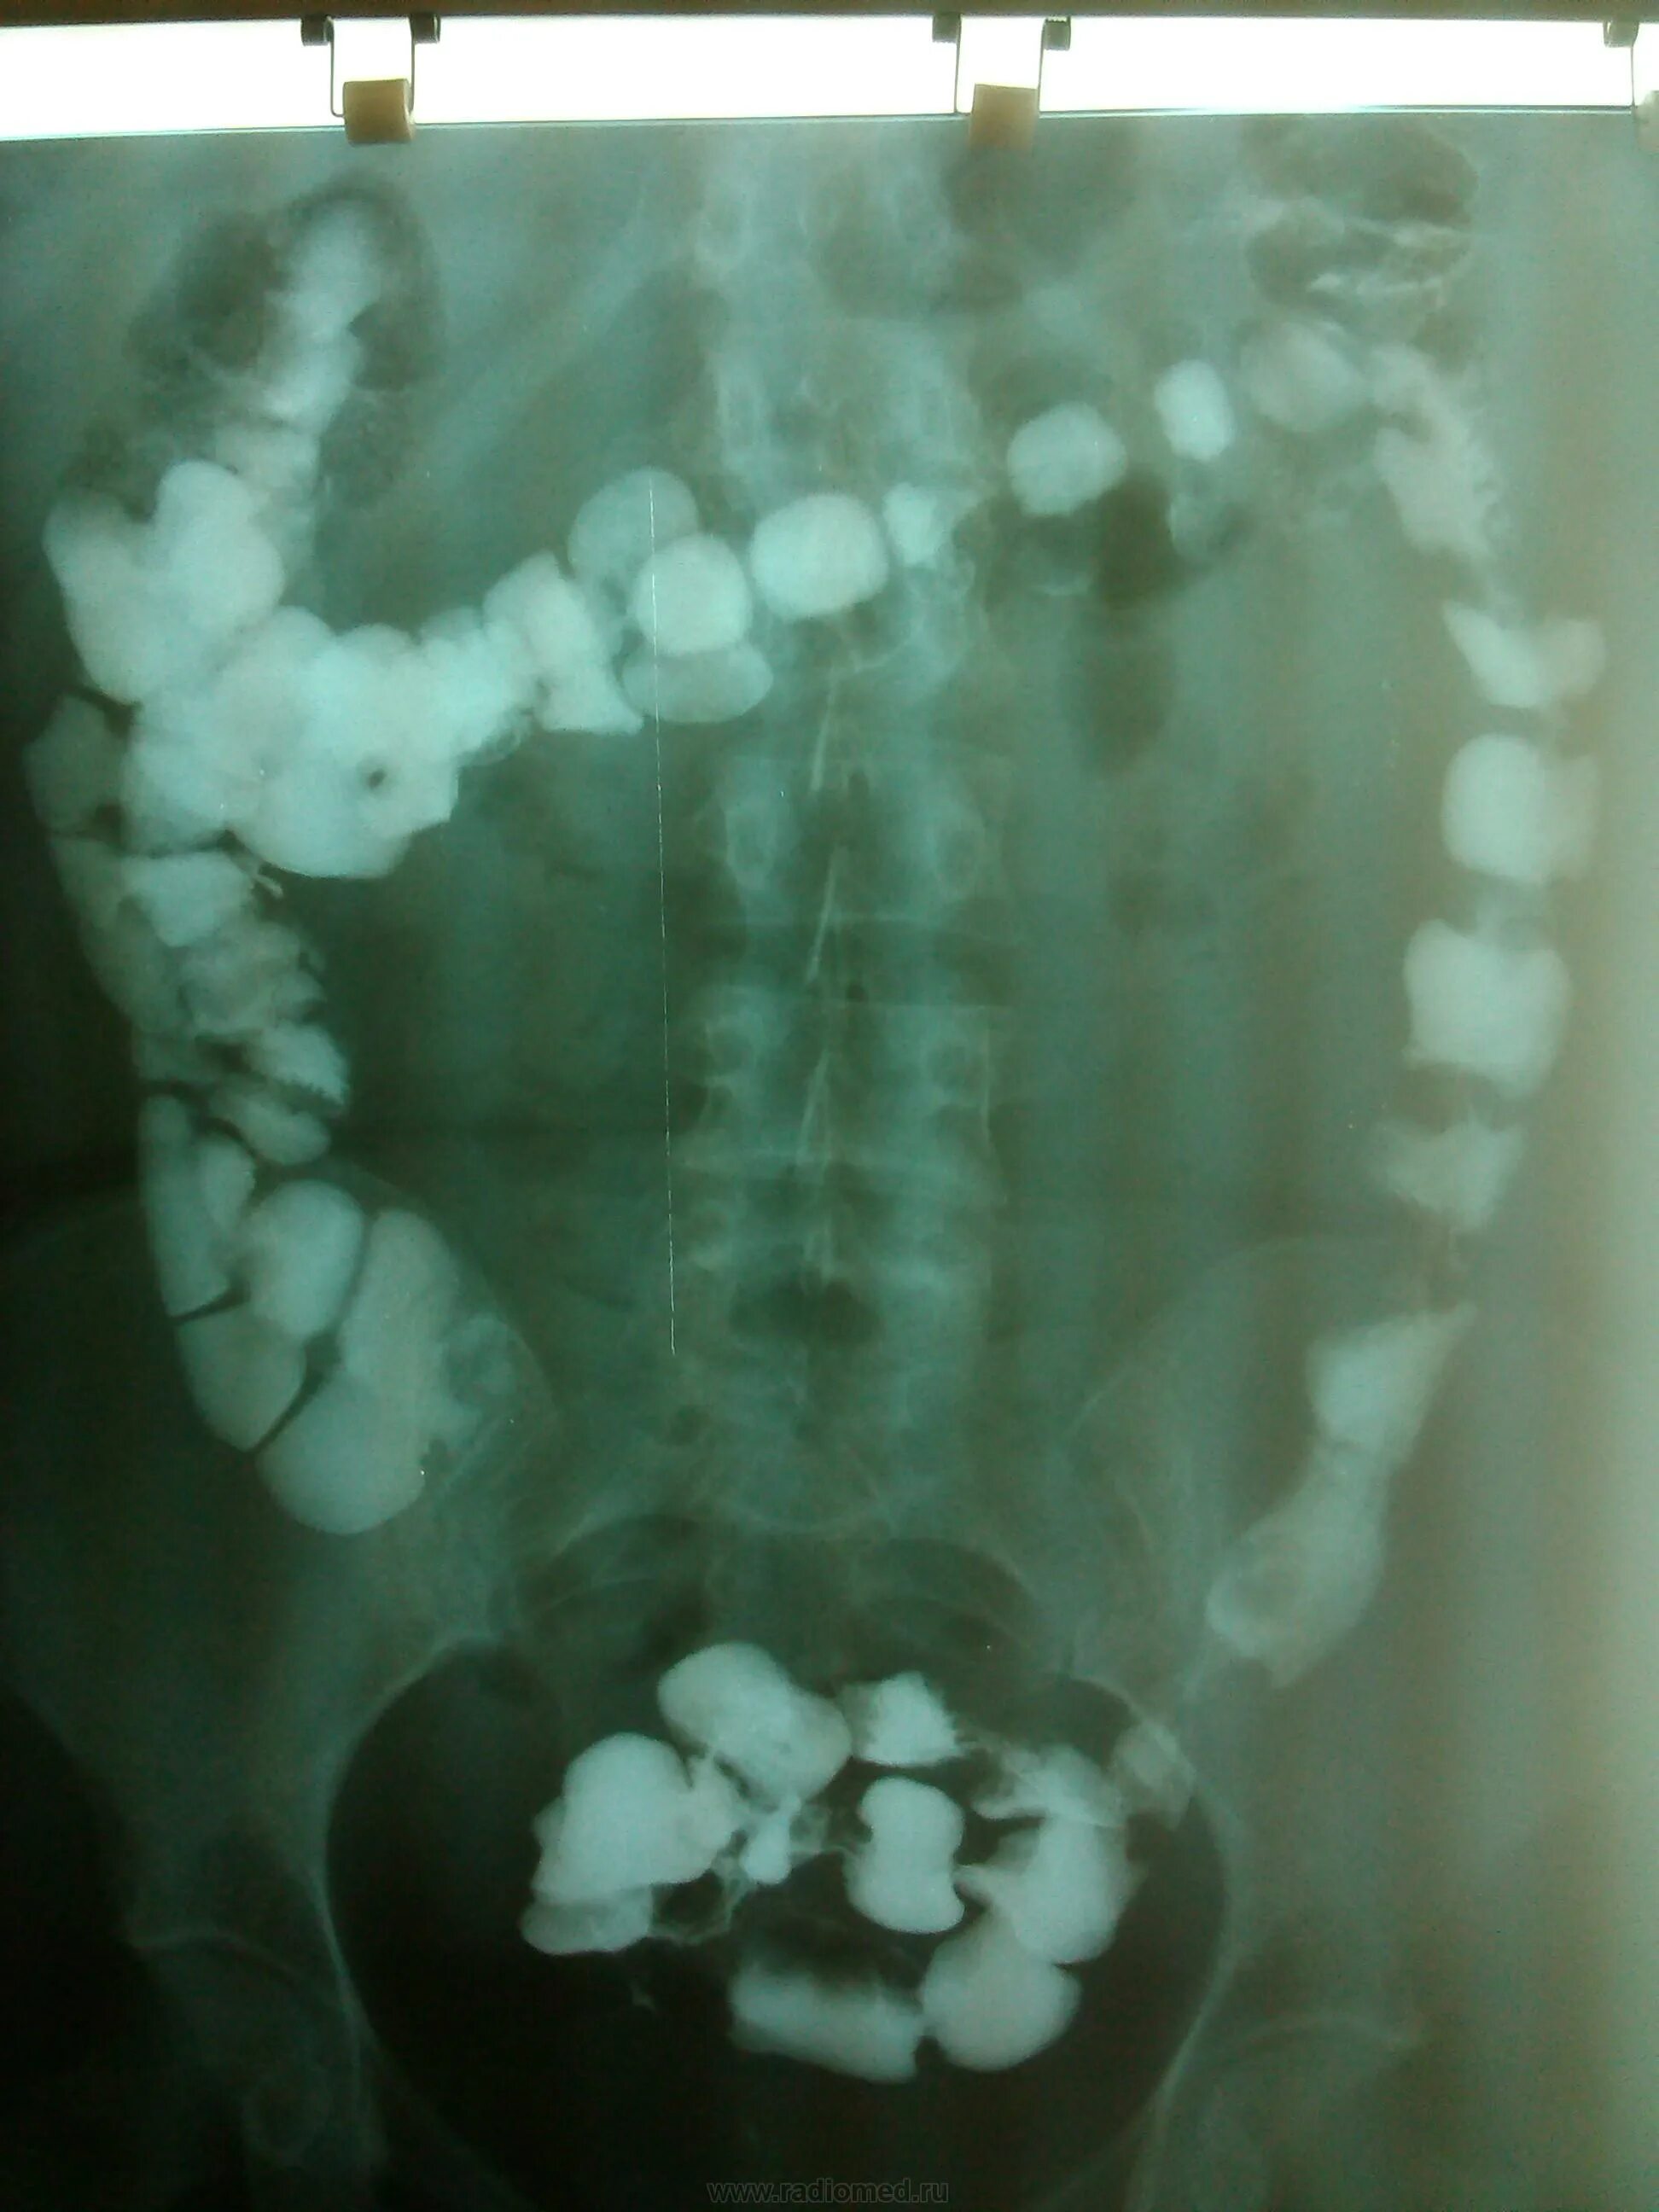

Долихоколон симптомы у взрослых